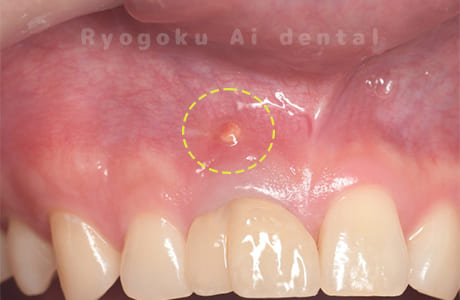

Case10

-

- 原因

- 下顎前歯部歯根嚢胞

- 治療内容

- 歯根端切除法

- 治療費用

- ¥77,000×2

他院で歯根端切除術を行ったが、良くならないとのことで、ご来院された患者様です。再根管治療後、サイナストラクトが消失しなかったため、歯根端切除術を行いました。現在、一年経過しておりますが、再発もせず、経過良好です。

<リスク・副作用>

外科手術のため、術後に出血、痛みや腫れ、違和感を伴います。口腔内の状態によっては適応できないことがあります。歯根端切除で治らなければ抜歯を検討しなくていけない場合もあります。